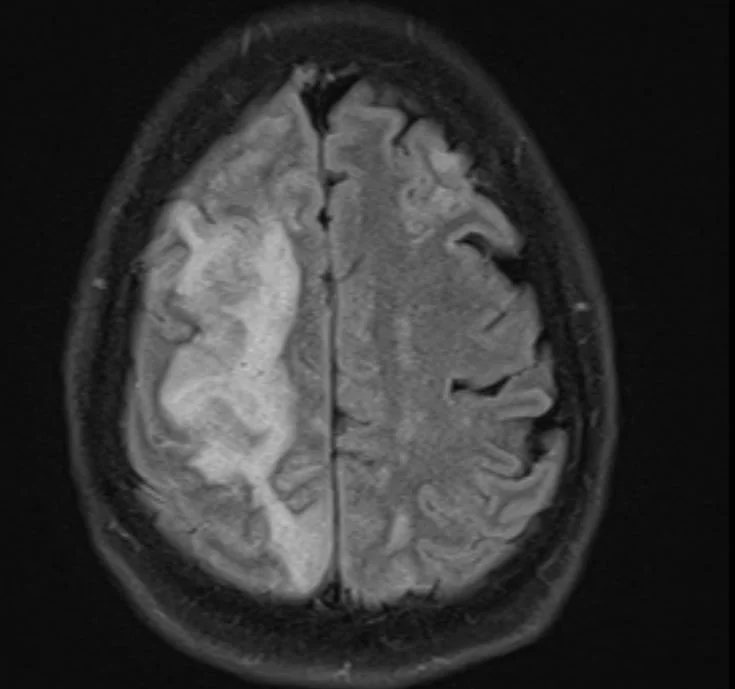

His MRI is shown below

what is the differential for the kind of stroke he suffered?

Our patient had an  atrio -esophageal fistula after his ablation and suffered an air embolus causing a stroke.